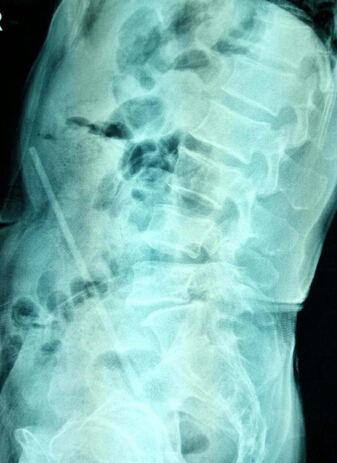

患者的腹部平片结果让所有人大吃一惊,原来患者的腹中有一根条索状的异物!

这是什么东西?如何进入腹中的?因为患者病史无法采集,一切都是一个谜……

历经二个多小时,曹烽主任带领科室团队凭借丰富的手术及临床经验,成功为患者实施手术。术中对所伤及肠管进行了修补,并取出一约20多厘米长的实物,令人惊叹!答案终于揭晓,与术前讨论方案一致。术中生命体征平稳,且出血量小无需输血,手术成功了!大家欢呼雷动,知情的医护也纷纷点赞祝贺!